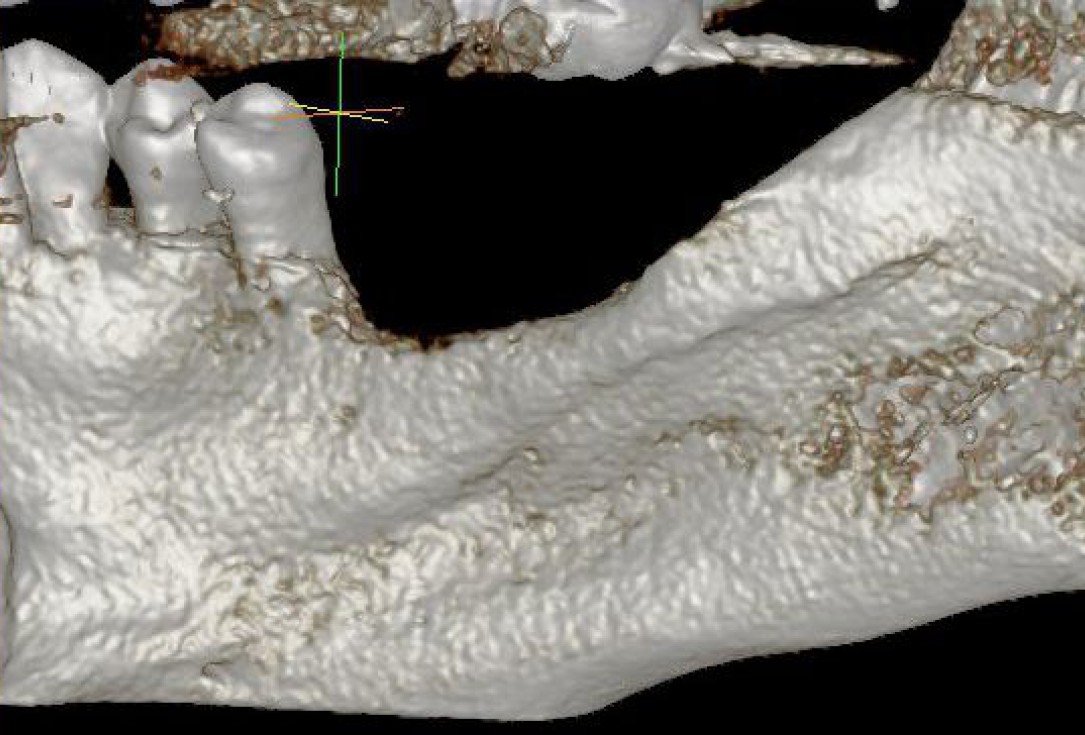

02/28 - Model of the initial defect computed from a CBCT scan - lingual viewThree-dimensional augmentation with maxgraft® cortico - Dr. R. Würdinger